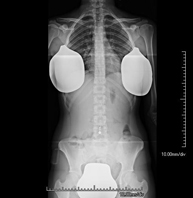

Tècnica que usa els raigs X a través de la qual s'obtenen imatges del sacre i del còccix per al seu estudi. Indicacions: traumatisme, dolor sacre o coccigi. - Telerradiologia columna

Tècnica que usa els raigs X a través de la qual s'obtenen imatges de tota la columna vertebral per al seu estudi, amb la valoració especialment de la presència d'escoliosi i dismetries pèlviques.

Una radiografia d'abdomen és una tècnica mitjançant la qual, amb l'ús d'una petita dosi de radiació, s'obté una imatge bidimensional de l'abdomen amb les seves estructures anatòmiques (estómac, intestí prim, intestí gros, fetge, pàncrees, ronyons, bufeta, pelvis òssia, etc.) - Telerradiologia columna

Tècnica que usa els raigs X a través de la qual s'obtenen imatges de tota la columna vertebral per al seu estudi, amb la valoració especialment de la presència d'escoliosi i dismetries pèlviques. - Telematria EEII (Extremitats Inferiors)